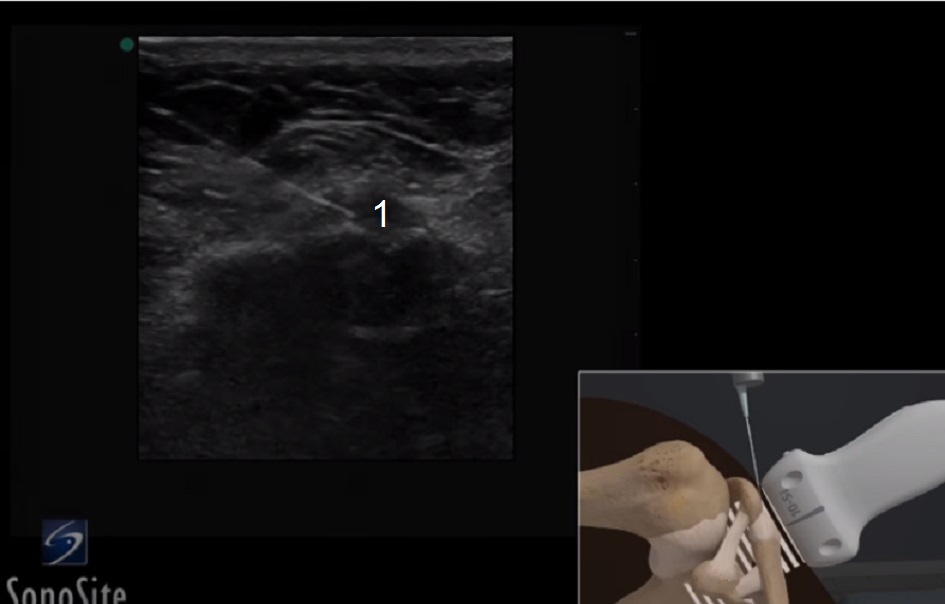

肩锁针尖图像

关节空间内的针头